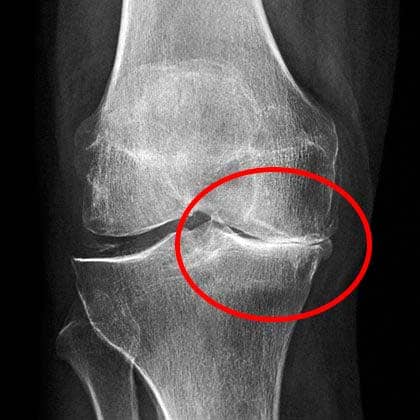

Dokter melihat hasil X-ray, lalu menyuruh saya agar berhenti mengangkat beban berat. Bahkan melarang mengangkat beban melebihi 2 kg!

Hasil X-ray menunjukkan problem serius di persendian lutut saya.